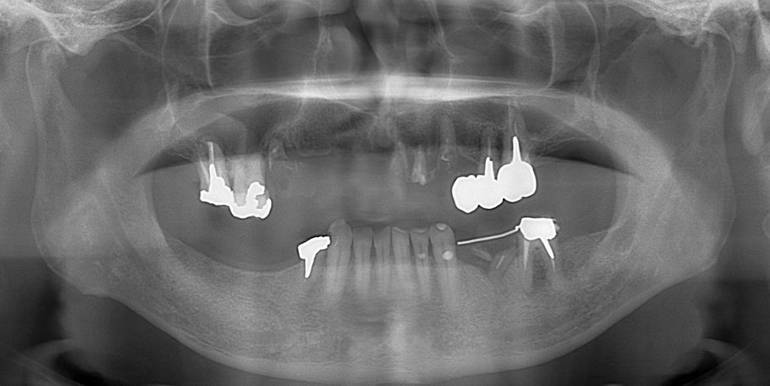

術前パノラマレントゲン写真。根の周りが黒くなり、骨がなくなっていることがわかります

治療後。歯周病で失われた骨が回復しています。使用インプラントはスプラインツイストです。